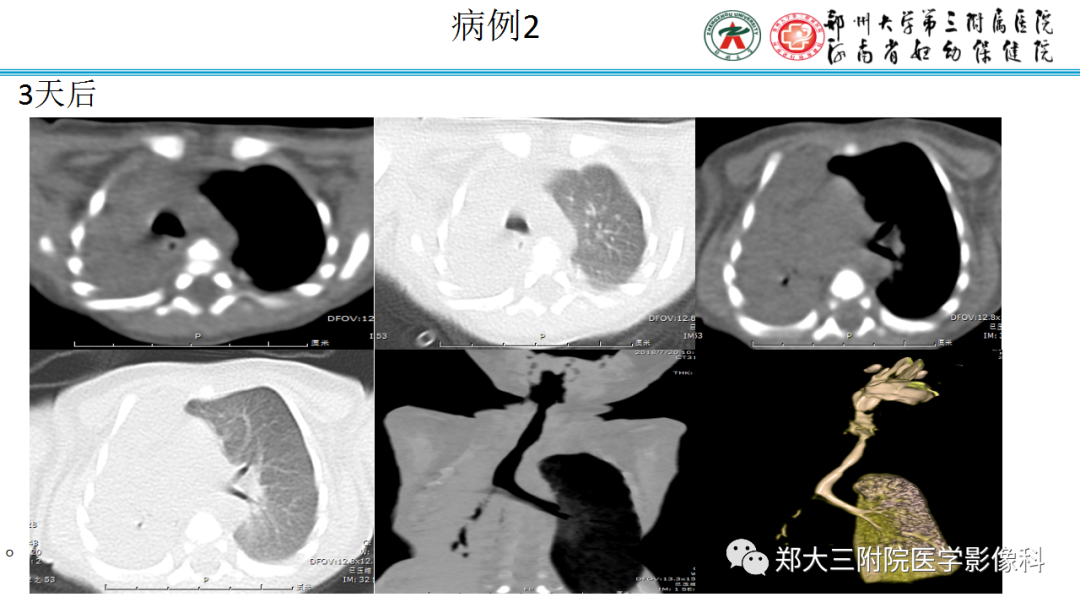

纵隔大细胞神经内分泌癌1例CT影像  张力性纵隔气肿影像表现及严重度分级